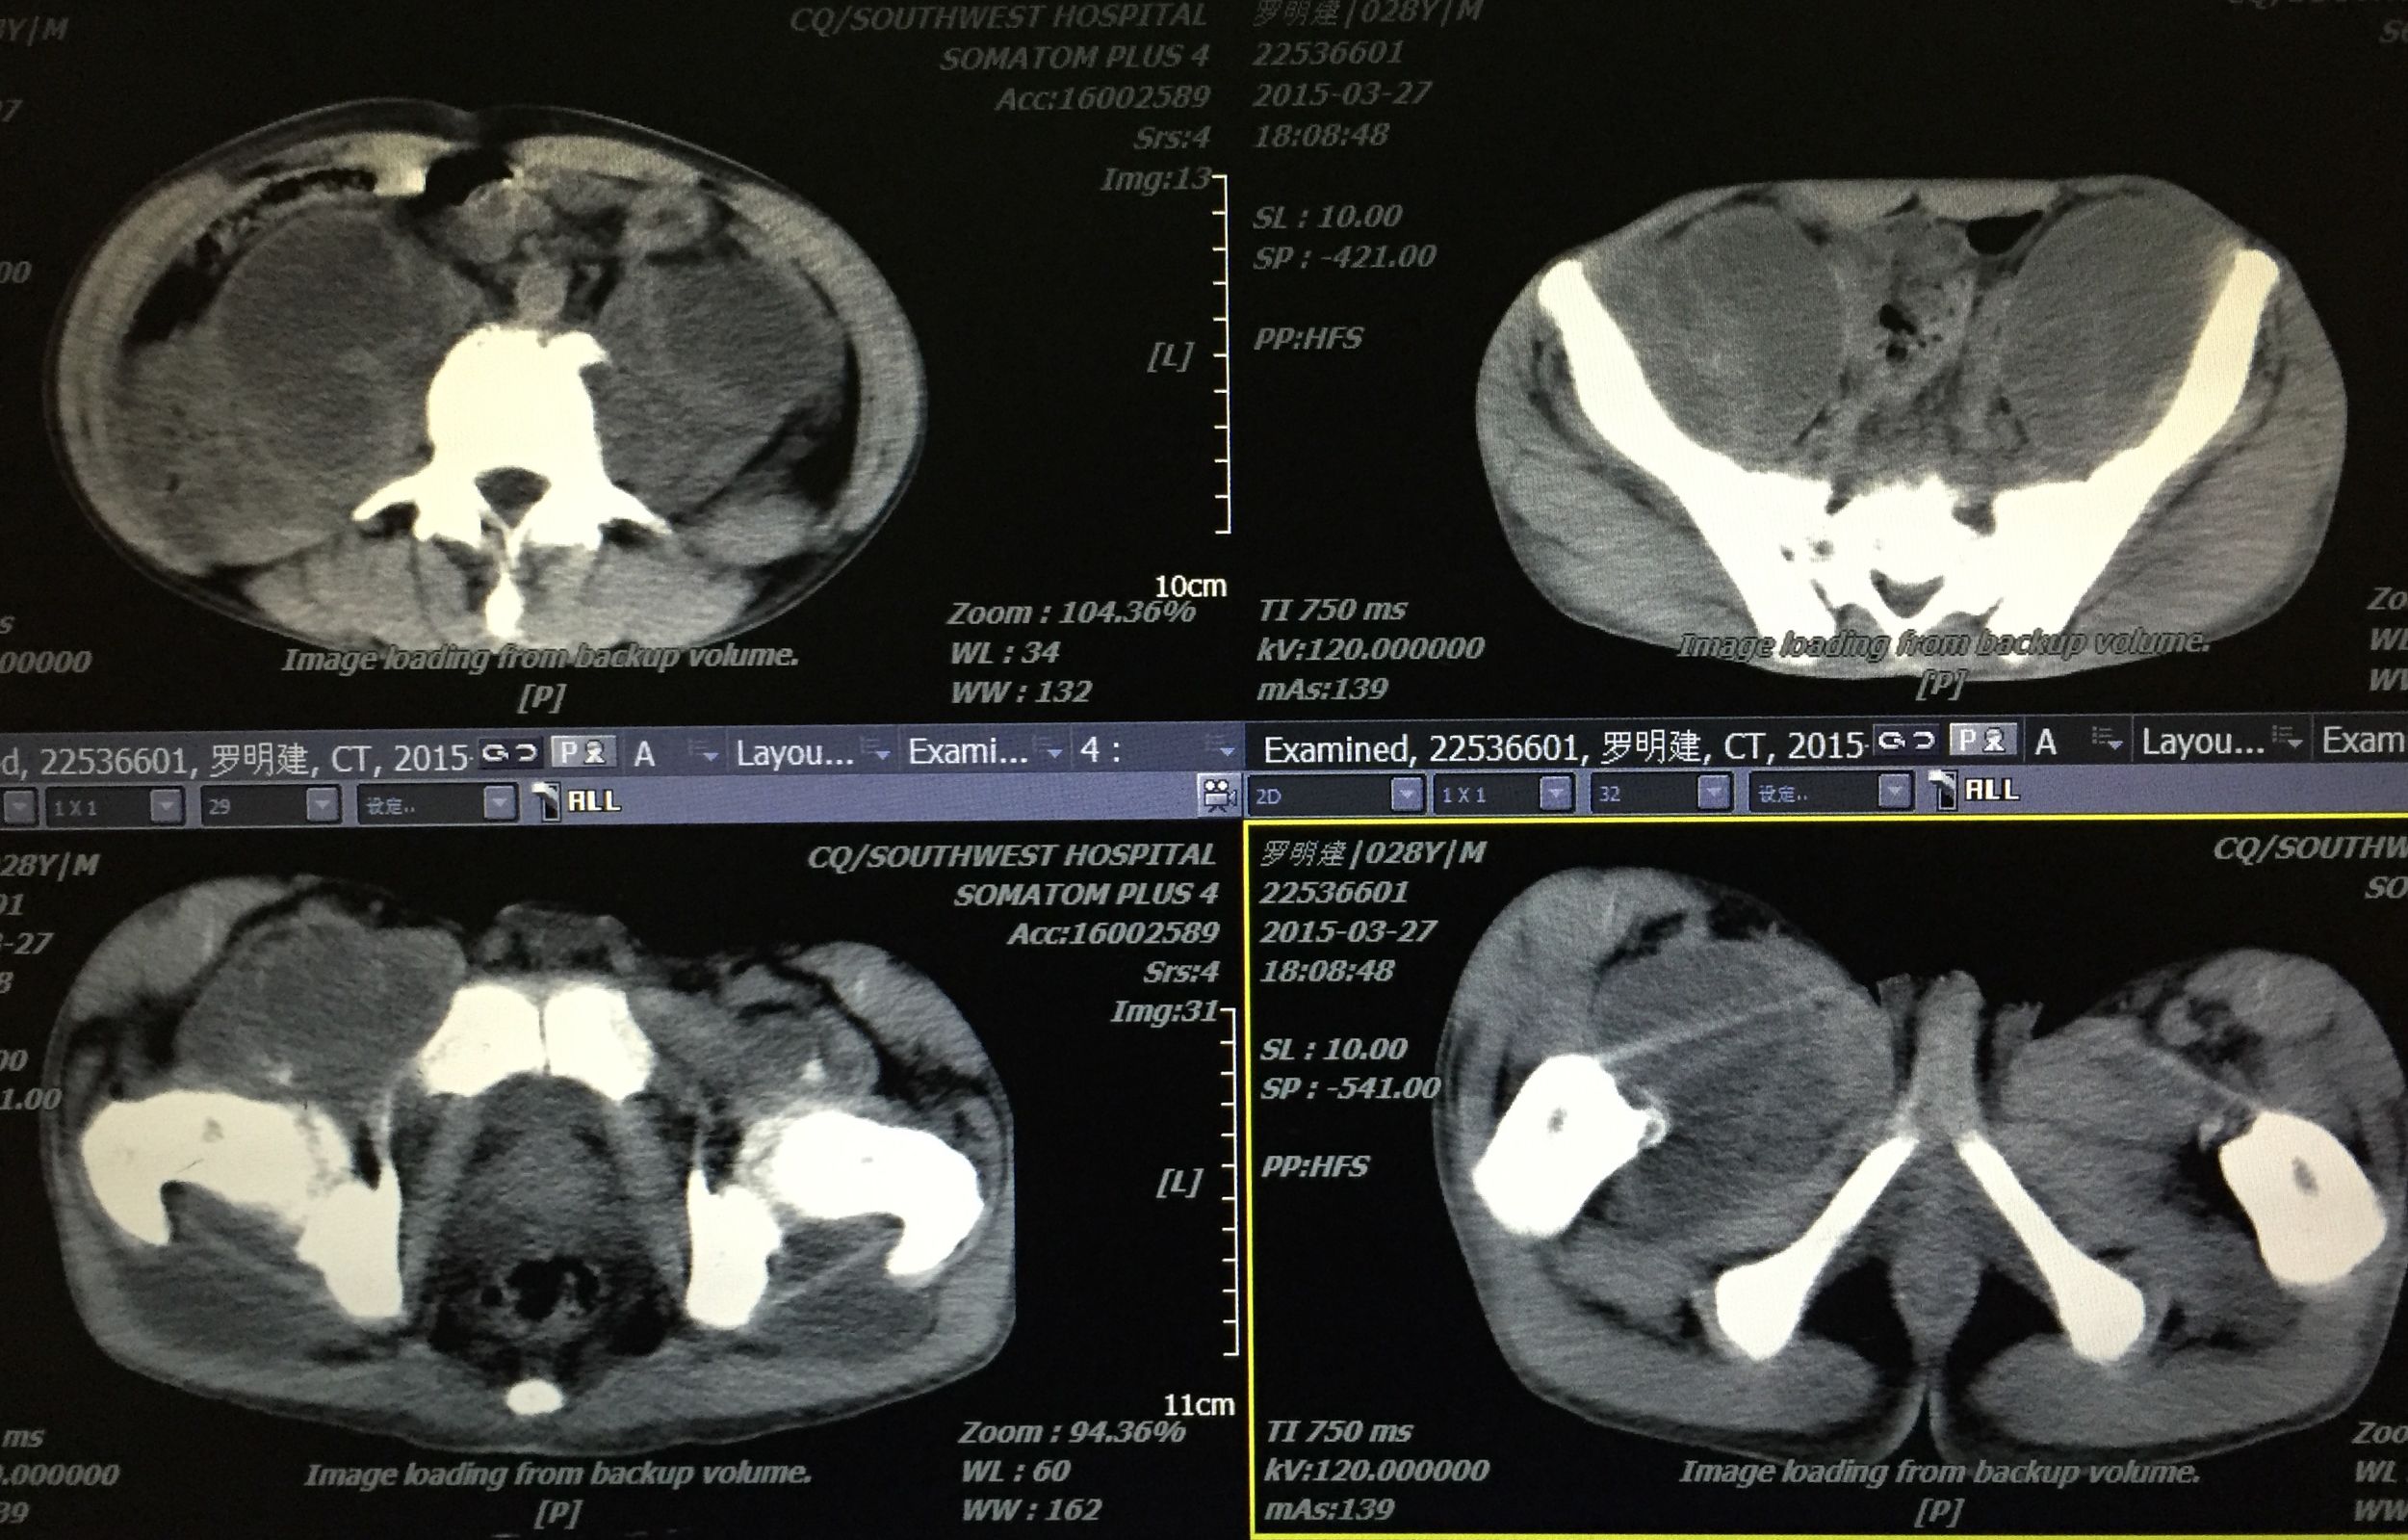

患者 29岁 盆腔及大腿根部多发结核脓肿(如图)

在门诊进行CT引导下穿刺引流术,植入五根引流管(如图白色条状物)

PS:结核脓肿出现,若能充分引流,可缩短预后时间。CT引导下穿刺引流是各部位脓肿引流较好的处理方案,微创、经济、患者耐受、门诊进行处理。